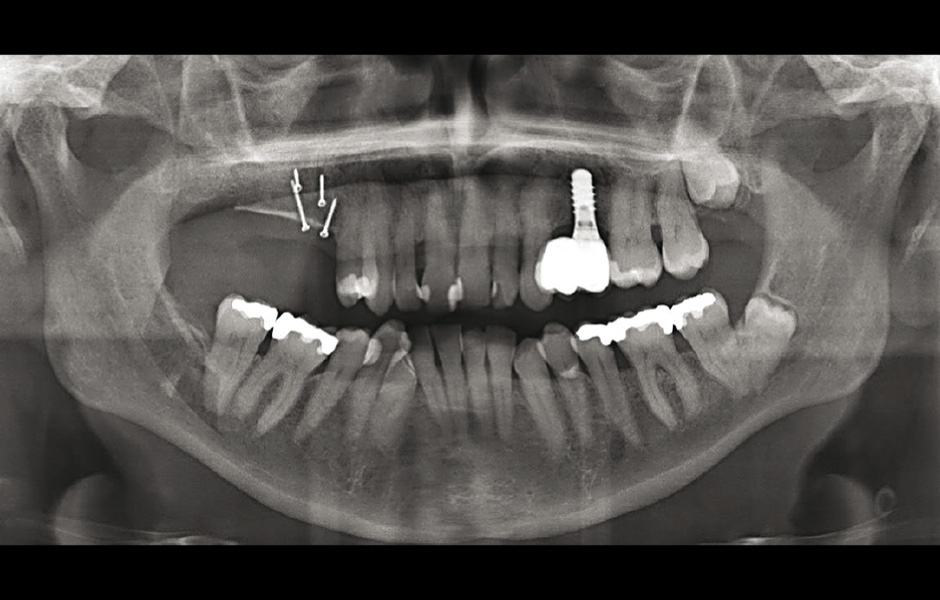

Obr. 13: Panoramatický snímek ukazuje úspěšnou vertikální augmentaci až na výšku alveolární kosti sousedních zubů.

Obr. 14: Tři měsíce po augmentaci byly úspěšně zavedeny dva implantáty.

Obr. 15: Panoramatický snímek po 5 letech: implantáty proteticky ošetřeny, oblast stabilní.